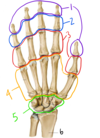

What structure is labeled by #8?

Long head of triceps brachii

Which structure is labeled by #40?

Flexor digitorum profundus

(The only muscle that can flex the fingers at the DIP joints!)

Together, the structures labeled #4 make up the…

Metacarpals

Fig. 11.5 Adapted from Gilroy et al. Atlas of Anatomy, second edition, Fig. 23.2.